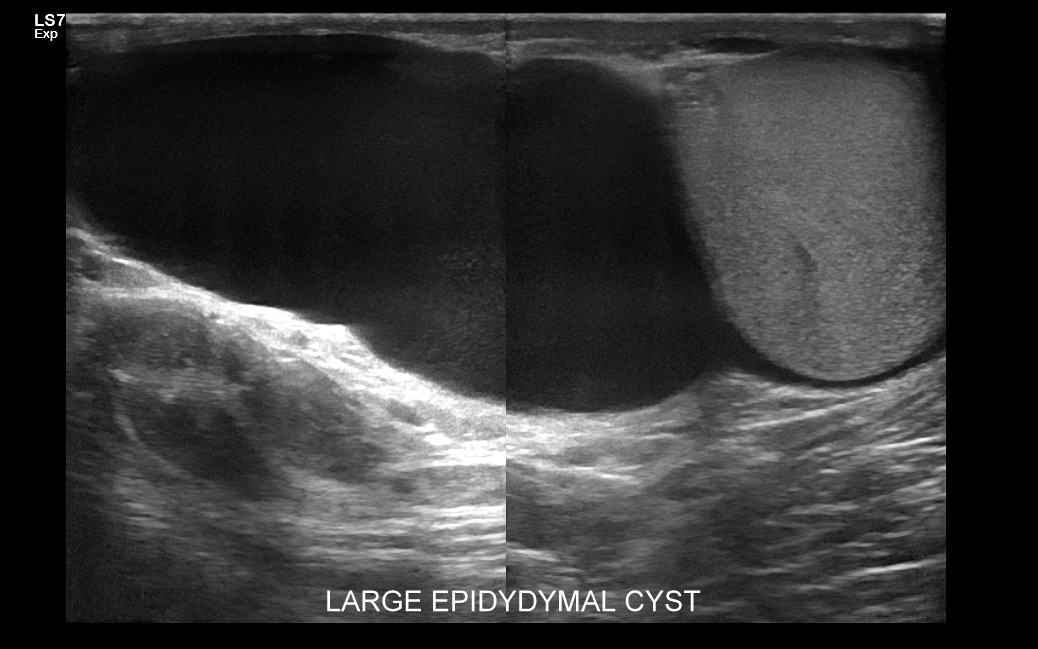

Najczęstsze choroby w obrębie moszny obejmują żylaki powrózka nasiennego, zapalenia jąder i najądrzy, wodniaki jądra, skręty szypuły jądra bądź przydatków jądra, torbiele najądrzy, nowotwory i raki jąder. Niezależnie od powyższego u chłopców spotyka się wnętrostwo, czyli niepełne zstąpienie jądra do moszny, które to może pozostać w jamie brzusznej lub pachwinie, a także ektopię jąder, czyli ich zabłąkane położenie (np. w okolicy krocza).